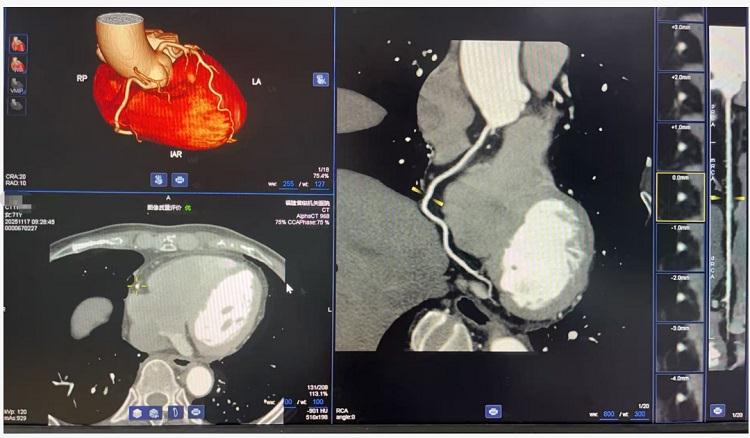

在临床应用方面,256排螺旋CT展现出广泛的适用性。设备可完成冠状动脉、头颈部血管的无创成像,清晰显示血管状况,为心脑血管疾病的早期筛查与诊断提供重要依据。在肿瘤诊疗领域,通过先进的三维重建技术,能够清晰呈现病灶细节,助力肿瘤精准分期和治疗方案制定。特别是在急诊急救方面,设备可快速完成多部位联合扫描,为胸痛、外伤等急症患者争取宝贵的救治时间。

冠状动脉CTA检查成像